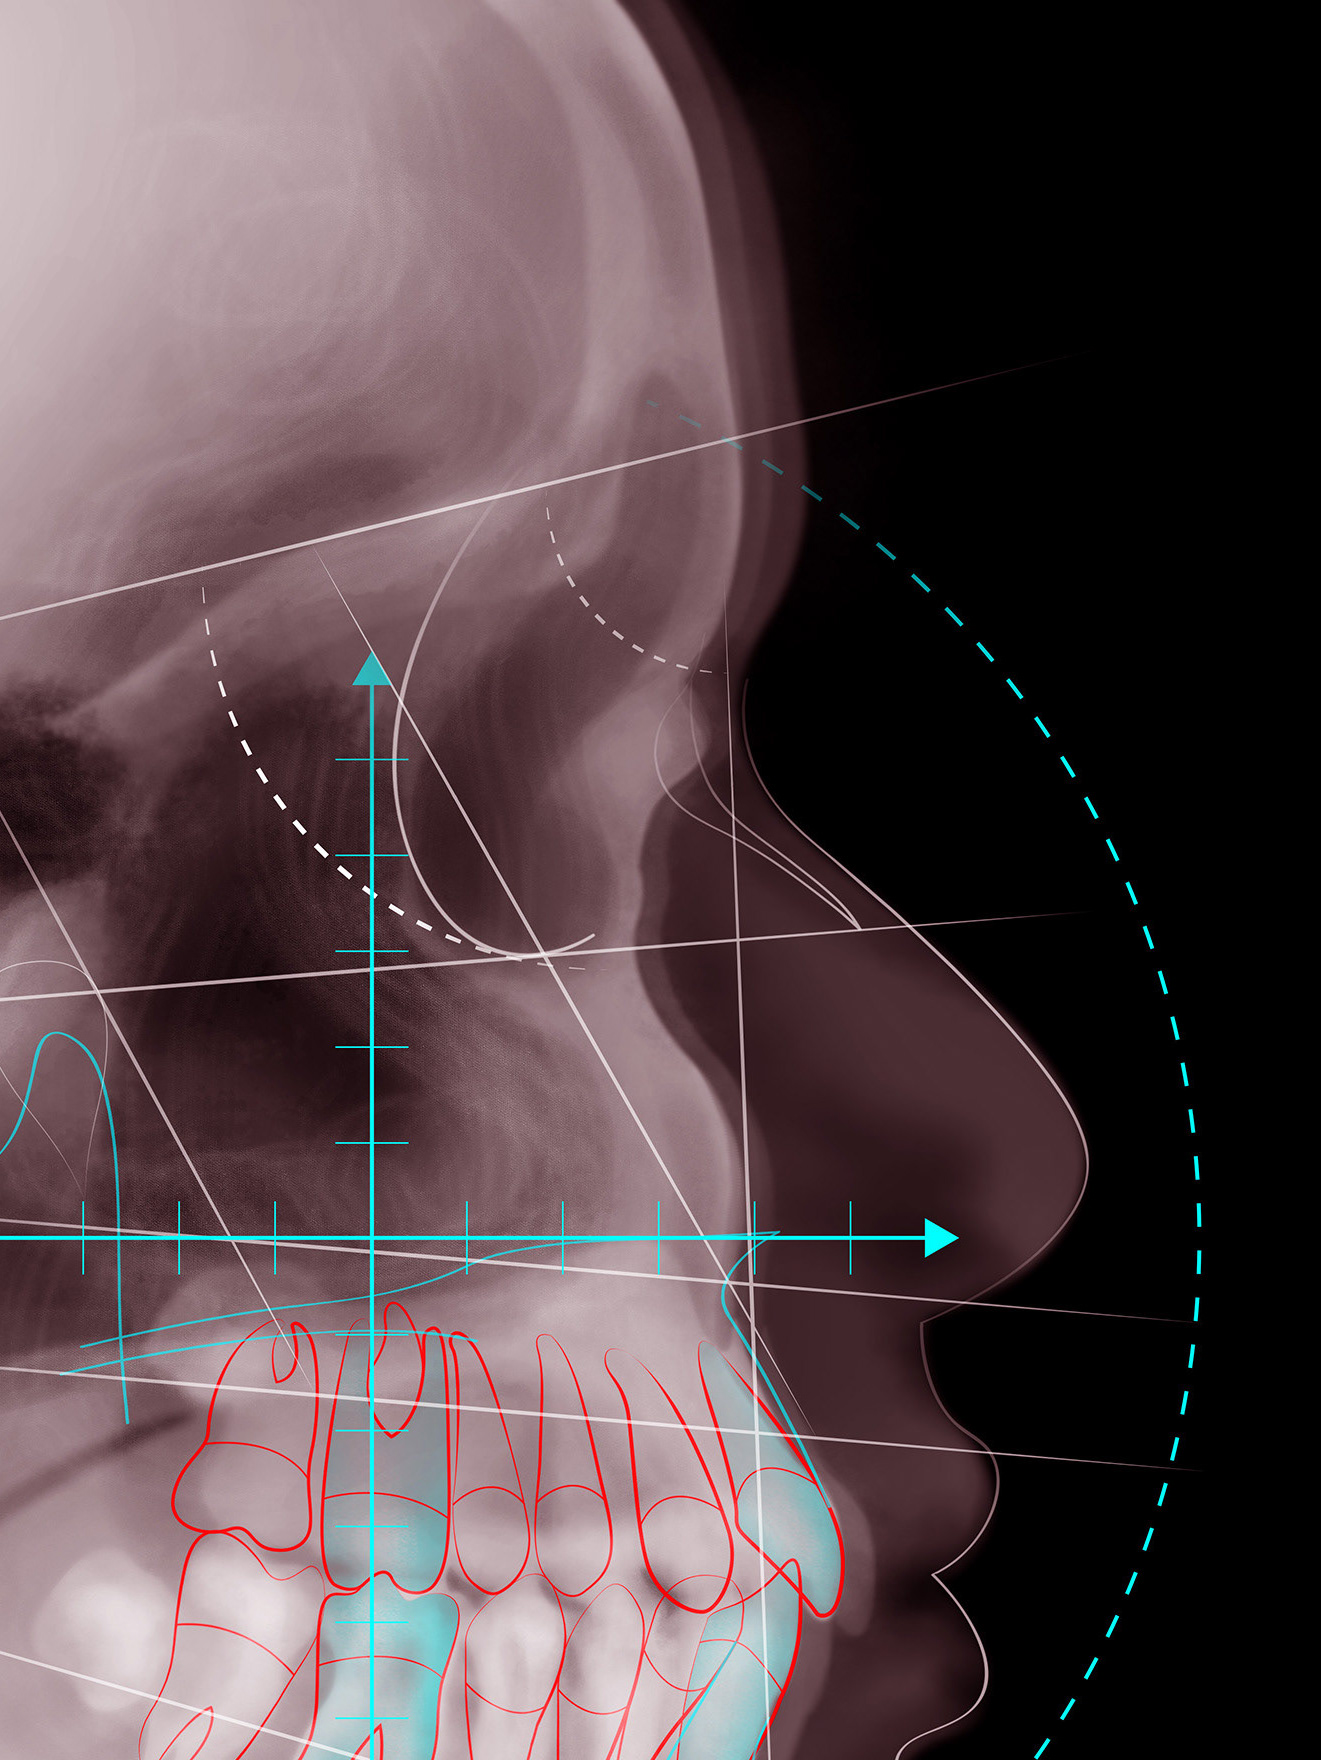

Cover Illustration - Dental Medicine magazine

2016